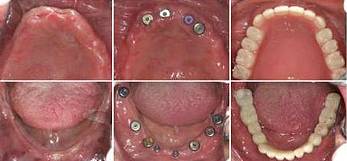

劉先生(花甲之年)全口牙缺失

步入花甲之年的劉先生其實(shí)在40多歲的時(shí)候牙齒就開始松動(dòng),起初想著還可以湊合吃飯,就沒(méi)有怎么管,可是如今年紀(jì)大了,牙齒一顆接著一顆的掉,只能喝粥。

△檢查CT片

△種植過(guò)程

劉先生的女兒看見(jiàn)父親在該享福的時(shí)候卻連頓好飯都吃不了,看在眼里,疼在心里,看到活動(dòng)就為父親報(bào)名了。

經(jīng)過(guò)2個(gè)多小時(shí)的種植過(guò)程,劉先生缺牙問(wèn)題解決了,當(dāng)天種好恢復(fù)咀嚼力?,F(xiàn)場(chǎng)露出一口整齊潔白的牙齒,笑著說(shuō):“有個(gè)孝順的女兒真是很大的福氣,現(xiàn)在終于可以好好的吃一頓飯了。”